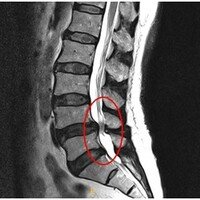

다리 마비 오면 감압술 덜 심하면 신경성형술

충남 보령에 사는 70대 송 할머니. 허리가 뻐근하고 엉덩이 윗부분이 쑤시는 증상이 몇 년 전부터 시작됐는데 나이가 들어 그러려니 하며 참고 지냈다. 몇 달 전부터는 엉덩이 아래쪽으로 허벅지, 종아리까지 땅기고 쑤시는 증세가 나타났…